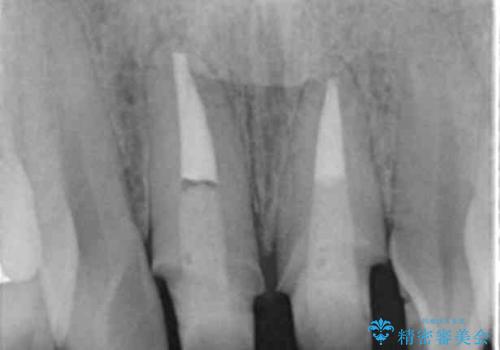

- 右上1+左上1/根管治療(保険),仮歯+ジルコニアクラウン(スペシャル):11,000円×2+130,000円×2 計282,000円(税別)費用は治療当時の料金となります

元々根管治療がされていたにも関わらず被せ物が作られておらず、このままではどんどん変色が進んでいってしまう状態でした。

歯をある程度削ることにはなりますが、被せ物にすることで歯の変色を隠し短期間でキレイな口元に仕上げることができました。